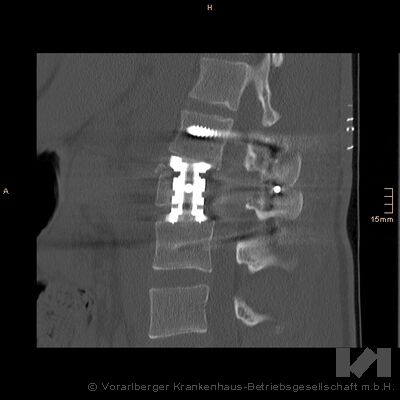

Was genau war passiert? Der 19jährige Skiurlauber Janis H. hatte beim Schifahren am Hochjoch im Montafon bei schlechter Sicht einen schweren Sturz erlitten. Er wurde am 21.Februar am Nachmittag per Helikopter ins LKH Feldkirch geflogen und aufgrund der schweren Rückenverletzung mit auftretender Lähmung sofort in den Schockraum gebracht. Die erste Diagnose ergab eine Querschnittlähmung ab dem zweiten Lendenwirbel. Sofort informierte das Schockraum-Team Wirbelsäulenspezialisten OA Dr. Meusburger zuhause, der sich umgehend auf den Weg ins Krankenhaus machte. Die Abklärung im Krankenhaus bestätigte dann den schweren neurologischen Schaden: „Konkret war der Spinalkanal der Wirbelsäule durch ein abgebrochenes Knochenstück zugemauert, das auf die Nervenstränge drückte. Der Patient konnte seine Beine nicht bewegen, zudem war keine Hautempfindung mehr gegeben. Diese klinische Diagnose wurde in der CT-Bildgebung bestätigt“, so Dr. Meusburger. Solche Verletzungen müssen unverzüglich behandelt werden, um die Chancen auf eine Erholung der komprimierten Nervenwurzeln zu erhöhen. Je länger der Schaden besteht, desto höher ist das Risiko eines bleibenden Querschnitts, weil durch die permanente Druckwirkung von außen die Nerven irreparabel geschädigt werden.

„Ich habe Janis unverzüglich operiert - den ersten Eingriff haben wir über den Rücken - also dorsal - vorgenommen. Wir haben den Spinalkanal freigelegt und vorsichtig die dort gelagerten Nervenbahnen zur Seite gehalten, um das Knochenstück, welches beim Sturz von der Wirbelhinterkante abgebrochen und in den Spinalkanal gelangt war, zu entfernen. Gleichzeitig wurde eine erste Stabilisierung des betroffenen Abschnitts der Lendenwirbelsäulen mit Schrauben und Metallstäben vorgenommen. Diese Operation dauerte ca. 4,5 Stunden. Ein zweiter Eingriff war dann eine Woche später noch notwendig, um den hochgradig zerstörten zweiten Lendenwirbel mit einem Cage (Implantat als Wirbelkörperersatz) als Stütze zu versehen. Dieser Cage wurde über einen linksseitigen Zugang hinter den Bauchorganen vorbei eingebracht“, erklärt der erfahrene Unfallchirurg Meusburger. Querschnittverletzungen in dieser Art werden am LKH Feldkirch ca.10 Mal pro Jahr operiert.